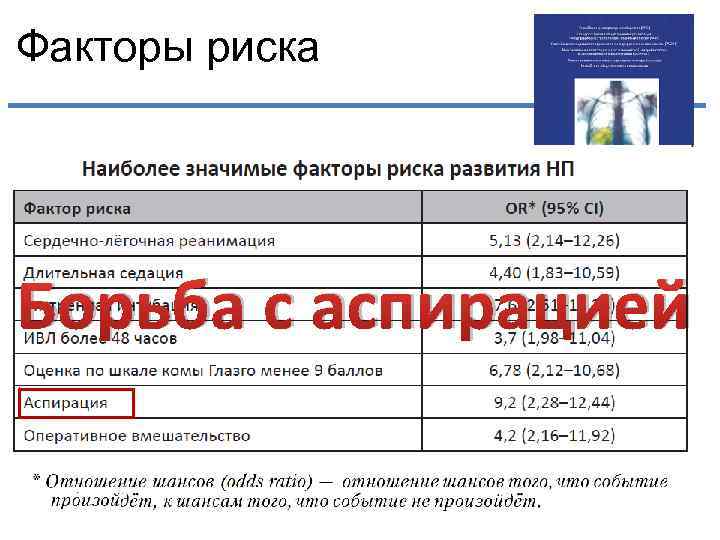

Факторы риска

Факторы риска

Факторы риска Борьба с аспирацией

Факторы риска Борьба с аспирацией

Факторы риска

Факторы риска